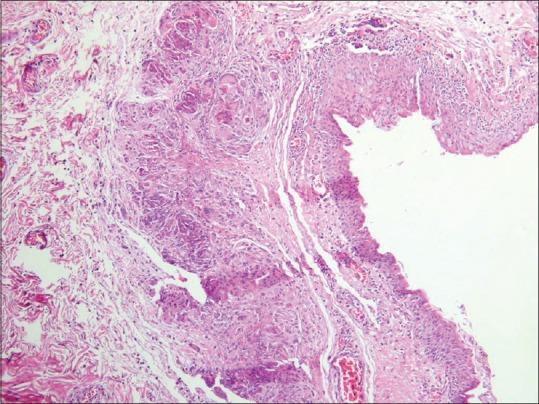

Allergic conjunctival granuloma is a rare cause of conjunctival ocular lesions. The aim of this case report was to present a successful treatment of an allergic conjunctival granuloma with topical tacrolimus eye drops. A 20-year-old female presented with bilateral multiple yellow nodules of the bulbar conjunctival epithelium and conjunctival injection. The patient had tearing, photophobia, itching, foreign body sensation, and red eye. The patient's signs and symptoms progressed despite the use of topical steroids. The patient was treated by application of tacrolimus eye drop (0.005%) in her right eye every 6 h while the left eye was put on placebo. Her signs and symptoms were recorded at each visit. After 3 weeks' therapy with topical tacrolimus eye drop, the patient became asymptomatic in her right eye and conjunctival granulomas fully resolved. Topical tacrolimus seems to be an effective therapeutic option for the treatment of allergic conjunctival granulomas.

过敏性结膜肉芽肿是一种罕见的结膜眼部病变原因。本病例报告的目的是介绍使用他克莫司眼药水成功治疗过敏性结膜肉芽肿。一名 20 岁女性因双侧球结膜上皮和结膜充血出现多发性黄色小结节就诊。患者有流泪、畏光、瘙痒、异物感和眼红。尽管使用了局部类固醇,但患者的体征和症状仍在加重。患者右眼每 6 小时使用他克莫司眼药水(0.005%)治疗,左眼使用安慰剂。每次就诊时都会记录患者的体征和症状。在使用他克莫司眼药水治疗 3 周后,患者右眼无症状,结膜肉芽肿完全消退。局部使用他克莫司似乎是治疗过敏性结膜肉芽肿的有效治疗选择。